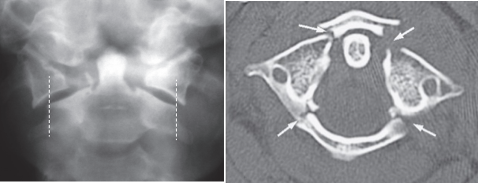

Jefferson fracture, burst fracture of C1

Blows to the top of the head (axial force) can result in fractures of the lateral masses of C1.

On the* open mouth view*, this fracture is suspected if the C1 lateral masses do not line up with the lateral borders of the C2 vertebral body .

Jefferson’s fracture. (a) Plain film showing overlap of the articular pillars of C1 beyond the margins of the C2 vertebral body (dashed lines) (b) Axial CT showing the fractures of the posterior arch more clearly together with fractures of the anterior arch (arrows)